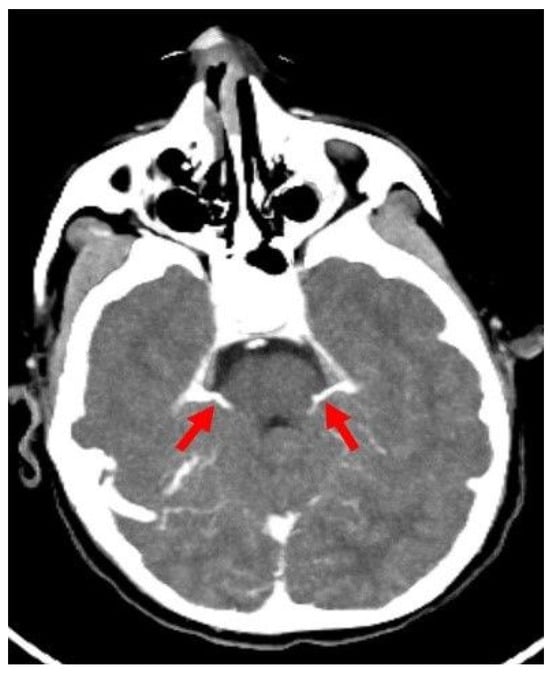

2.2. Preliminary Anatomical Study of Infratentorial Veins in Children

- ICV-SPV: Absence of opacification in the ICVs and SPVs in the venous phase, based on the revised venous scoring system by Marchand et al. [10].

- Srairi, M.; Meluchova, Z.; Paoletti, M.; Ahmad, M.; Abaziou, T.; Atthar, V.; Gilles Georget, G.; Mrozek, S.; Larcher, C.; Osinski, D.; et al. Diagnostic accuracy of a revised computed tomography angiography score for brain death confirmation, combining supra-tentorial arteries and infratentorial veins. Eur. J. Radiol. 2020, 130, 109132. [Google Scholar] [CrossRef] [PubMed]